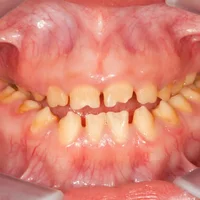

Amélogenèse imparfaite